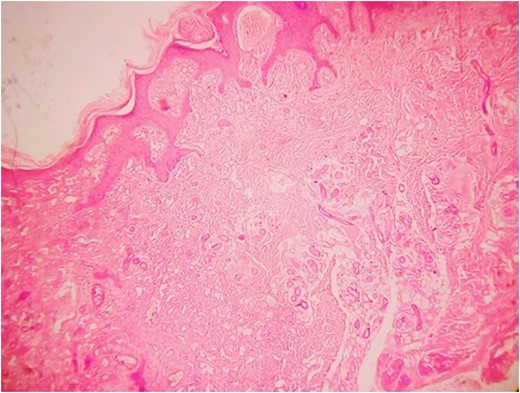

The superficial layer of the lesion showing angiokeratoma (haematoxylin and eosin).

Histopathology examination revealed grayish white to grayish brown lesions with hyperkeratitis of the epidermis and focally hyperplastic stratified squamous epithelium. Papillary dermis with numerous dilated, thin walled congested capillaries and the deep dermis with increased number of eccrine glands and numerous capillary channels intermingled with eccrine structure. The stroma was composed of fibrofatty tissue along with few pilar structures with the focal distribution of granulation tissue. Such a histological picture was found to be consistent with a diagnosis of EAKH.